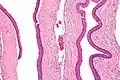

Micrograph of an odontogenic keratocyst. H&E stain. |

Histology

Odontogenic keratocysts have a diagnostic histological appearance. Under the microscope, OKCs vaguely resemble keratinized squamous epithelium;[14] however, they lack rete ridges and often have an artifactual separation from their basement membrane.[2]

The fibrous wall of the cyst is usually thin and uninflamed. The epithelial lining is thin with even thickness and parakeratinised with columnar cells in the basal layer which have focal reverse polarisation (nuclei are on the opposite pole of the cell).[12] The basal cells are an indication of the odontogenic origin as they resemble pre-ameloblasts. The epithelium can separate from the wall, resulting in islands of epithelium. These can go on to form 'satellite' or 'daughter' cysts, leading to an overall multilocular cyst.[9] Presence of daughter cysts is particularly seen in those with NBCCS.[12] Inflamed cysts show hyperplastic epithelium which is no longer characteristic of OKCs and can have resemblance to radicular cysts instead. Due to areas of focal inflammation, a larger biopsy is required for correct diagnosis of odontogenic keratocysts.[9]